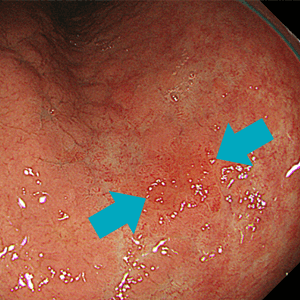

当院で採用している内視鏡システムであるEVIS X1は、高精細画像での撮像ができるだけでなく、狭帯域光観察(narrow band imaging, NBI)の性能も非常に高いものとなっているため、通常発見しにくいような早期のがんなどの病変も明瞭に描出することができるようになっています。

通常光(白色光)観察ではやや不明瞭な早期胃がん病変ですが通常光(白色光)観察ではやや不明瞭な早期胃がん病変ですが

NBI観察では明瞭化しています。NBI観察では明瞭化しています。